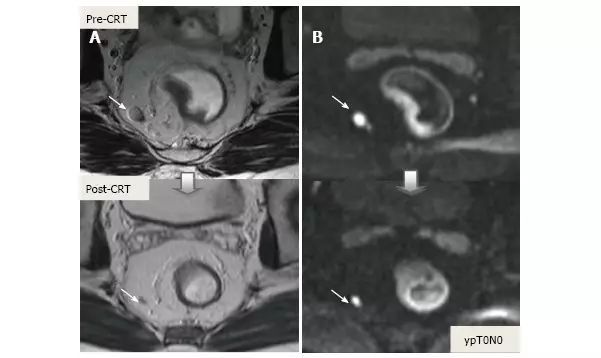

图片

图 18. DWI 对放化疗后为 ypT3 的肿瘤重新分期。A. T2 加权轴位显示治疗后半圆形浸润肿瘤,与残留的 T3 肿瘤相符(箭头);B. 治疗后 DWI;C. ADC,图像分别对应肿瘤的高低信号强度,治疗前后 ADC 值分别为 0.68-0.72 和 1.22-1.44×10-3 mm²/s,治疗后 ADC 值增加与治疗反应相符。

图 19. DWI 对放化疗后 ypT0 直肠肿瘤重新分期。A. 治疗后 T2 加权轴位图像显示,先前直肠肿瘤区域的低信号强度纤维化厚壁(箭头),难以确定该区域是否含有肿瘤细胞还是完全缓解;B. 在治疗后 DW 图像(B-800)中,在以前的肿瘤区域(箭头)没有弥散信号,与完全缓解相符。在这种情况下,DWI 正确区分肿瘤与纤维化;C. ADC 图像显示治疗后平均 ADC 增加(0.70 × 10-3 mm²/s 对比 1.40 × 10-3 mm²/s)与治疗反应相符,但不能预测完全缓解。